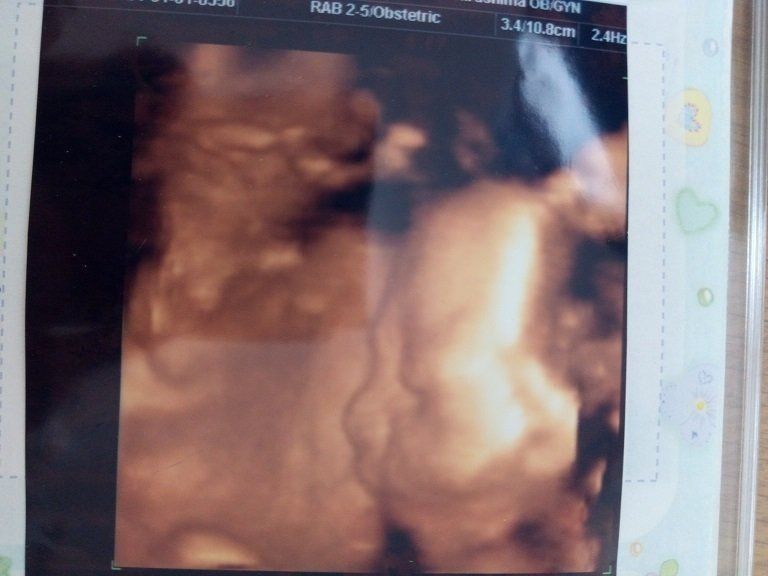

妊娠26週のエコー写真 4Dエコーに感動

初めて4Dのエコーで検査をしました。この日に性別を教えてもらえることになっていたので、とても楽しみに臨んだ検査では、股をしっかり開いて「男の子」を主張してくれました。右側に映るのが赤ちゃんの横顔です。顔がはっきりと見え、嬉しくて何度も見返していました。でも鼻が低いのが私に似ているようで、「可哀そうに」とも思っていました。